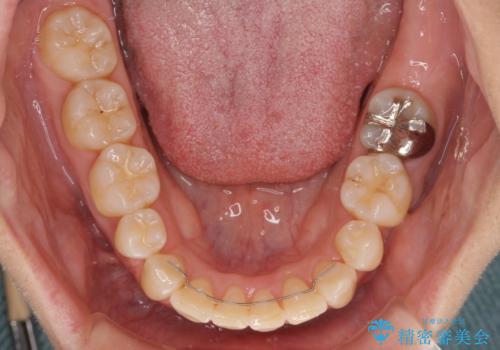

前歯のデコボコを抜歯矯正で改善 メタル装置で費用を抑える

- 前歯のデコボコと口元の突出感を気にして来院された患者様です。

非抜歯矯正ではデコボコを解消することでより口元が突出してしまうため、上下左右の小臼歯4本の抜歯を行い、ワイヤー装置による矯正治療を行うこととしました。

もう少し口元の突出感を改善したかったのですが、舌の突出癖が影響し下顎前歯が唇側に押させる仕上がりとなりました。